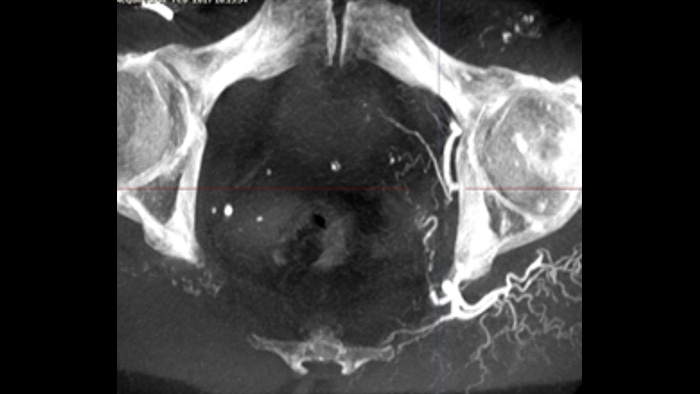

Le système XperGuide offre un guidage de l’aiguille sur les images en 3D et en temps réel, ce qui vous permet de réaliser des procédures percutanées nécessitant l’utilisation d’une aiguille en salle hybride. Il superpose les images de fluoroscopie en temps réel aux données 3D issues de l’imagerie des tissus mous des acquisitions TDM ou IRM ou de Philips XperCT précédentes, et fournit des informations sur la trajectoire et la cible de l’aiguille.